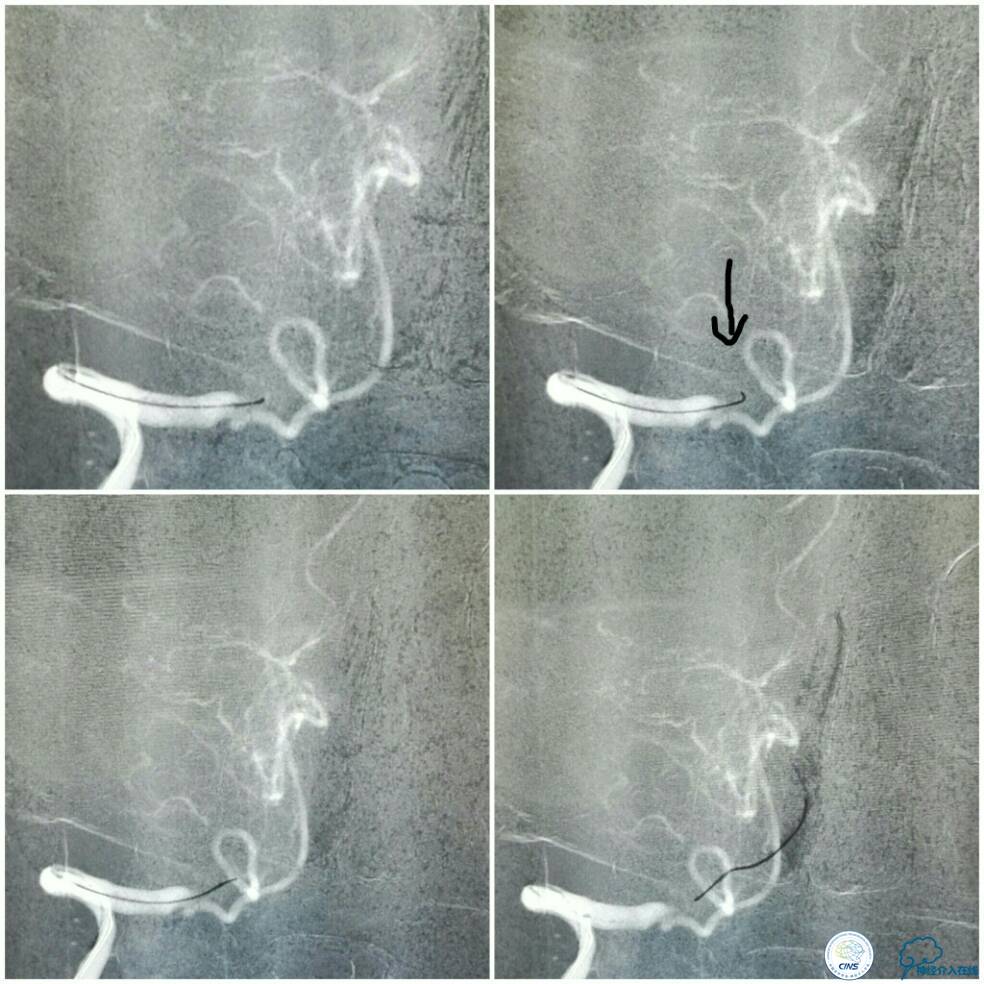

同期行DSA提示右椎动脉V4段发出右PICA后未见顺行显影(图2),左椎动脉V4段-基底动脉汇合处重度狭窄(图3),前循环向后循环的未见明显代偿(图4)。

全麻下双股动脉穿刺,分别置入6F及5F动脉鞘。6F导引导管置于右椎动脉V2段,Traxcess 微导丝与Echelon 10微导管同轴,经多次尝试后送达基底动脉(图8);操作过程中见微导丝头端打折变向,此时手控导丝有阻力感,考虑是闭塞病变的近心端(图8箭头),当微导丝越过闭塞段进入血栓,此时微导丝及微管前行无明显阻力。

微导管造影证实在基底动脉真腔后,交换技术送入Transend微导丝(0.014″300 cm)至左侧大脑后动脉P1段,送入Gateway球囊(2.0 mm×9.0 mm)从闭塞段远端向近心端扩张4次,扩张完造影示右椎动脉V4段无再通(图9)。